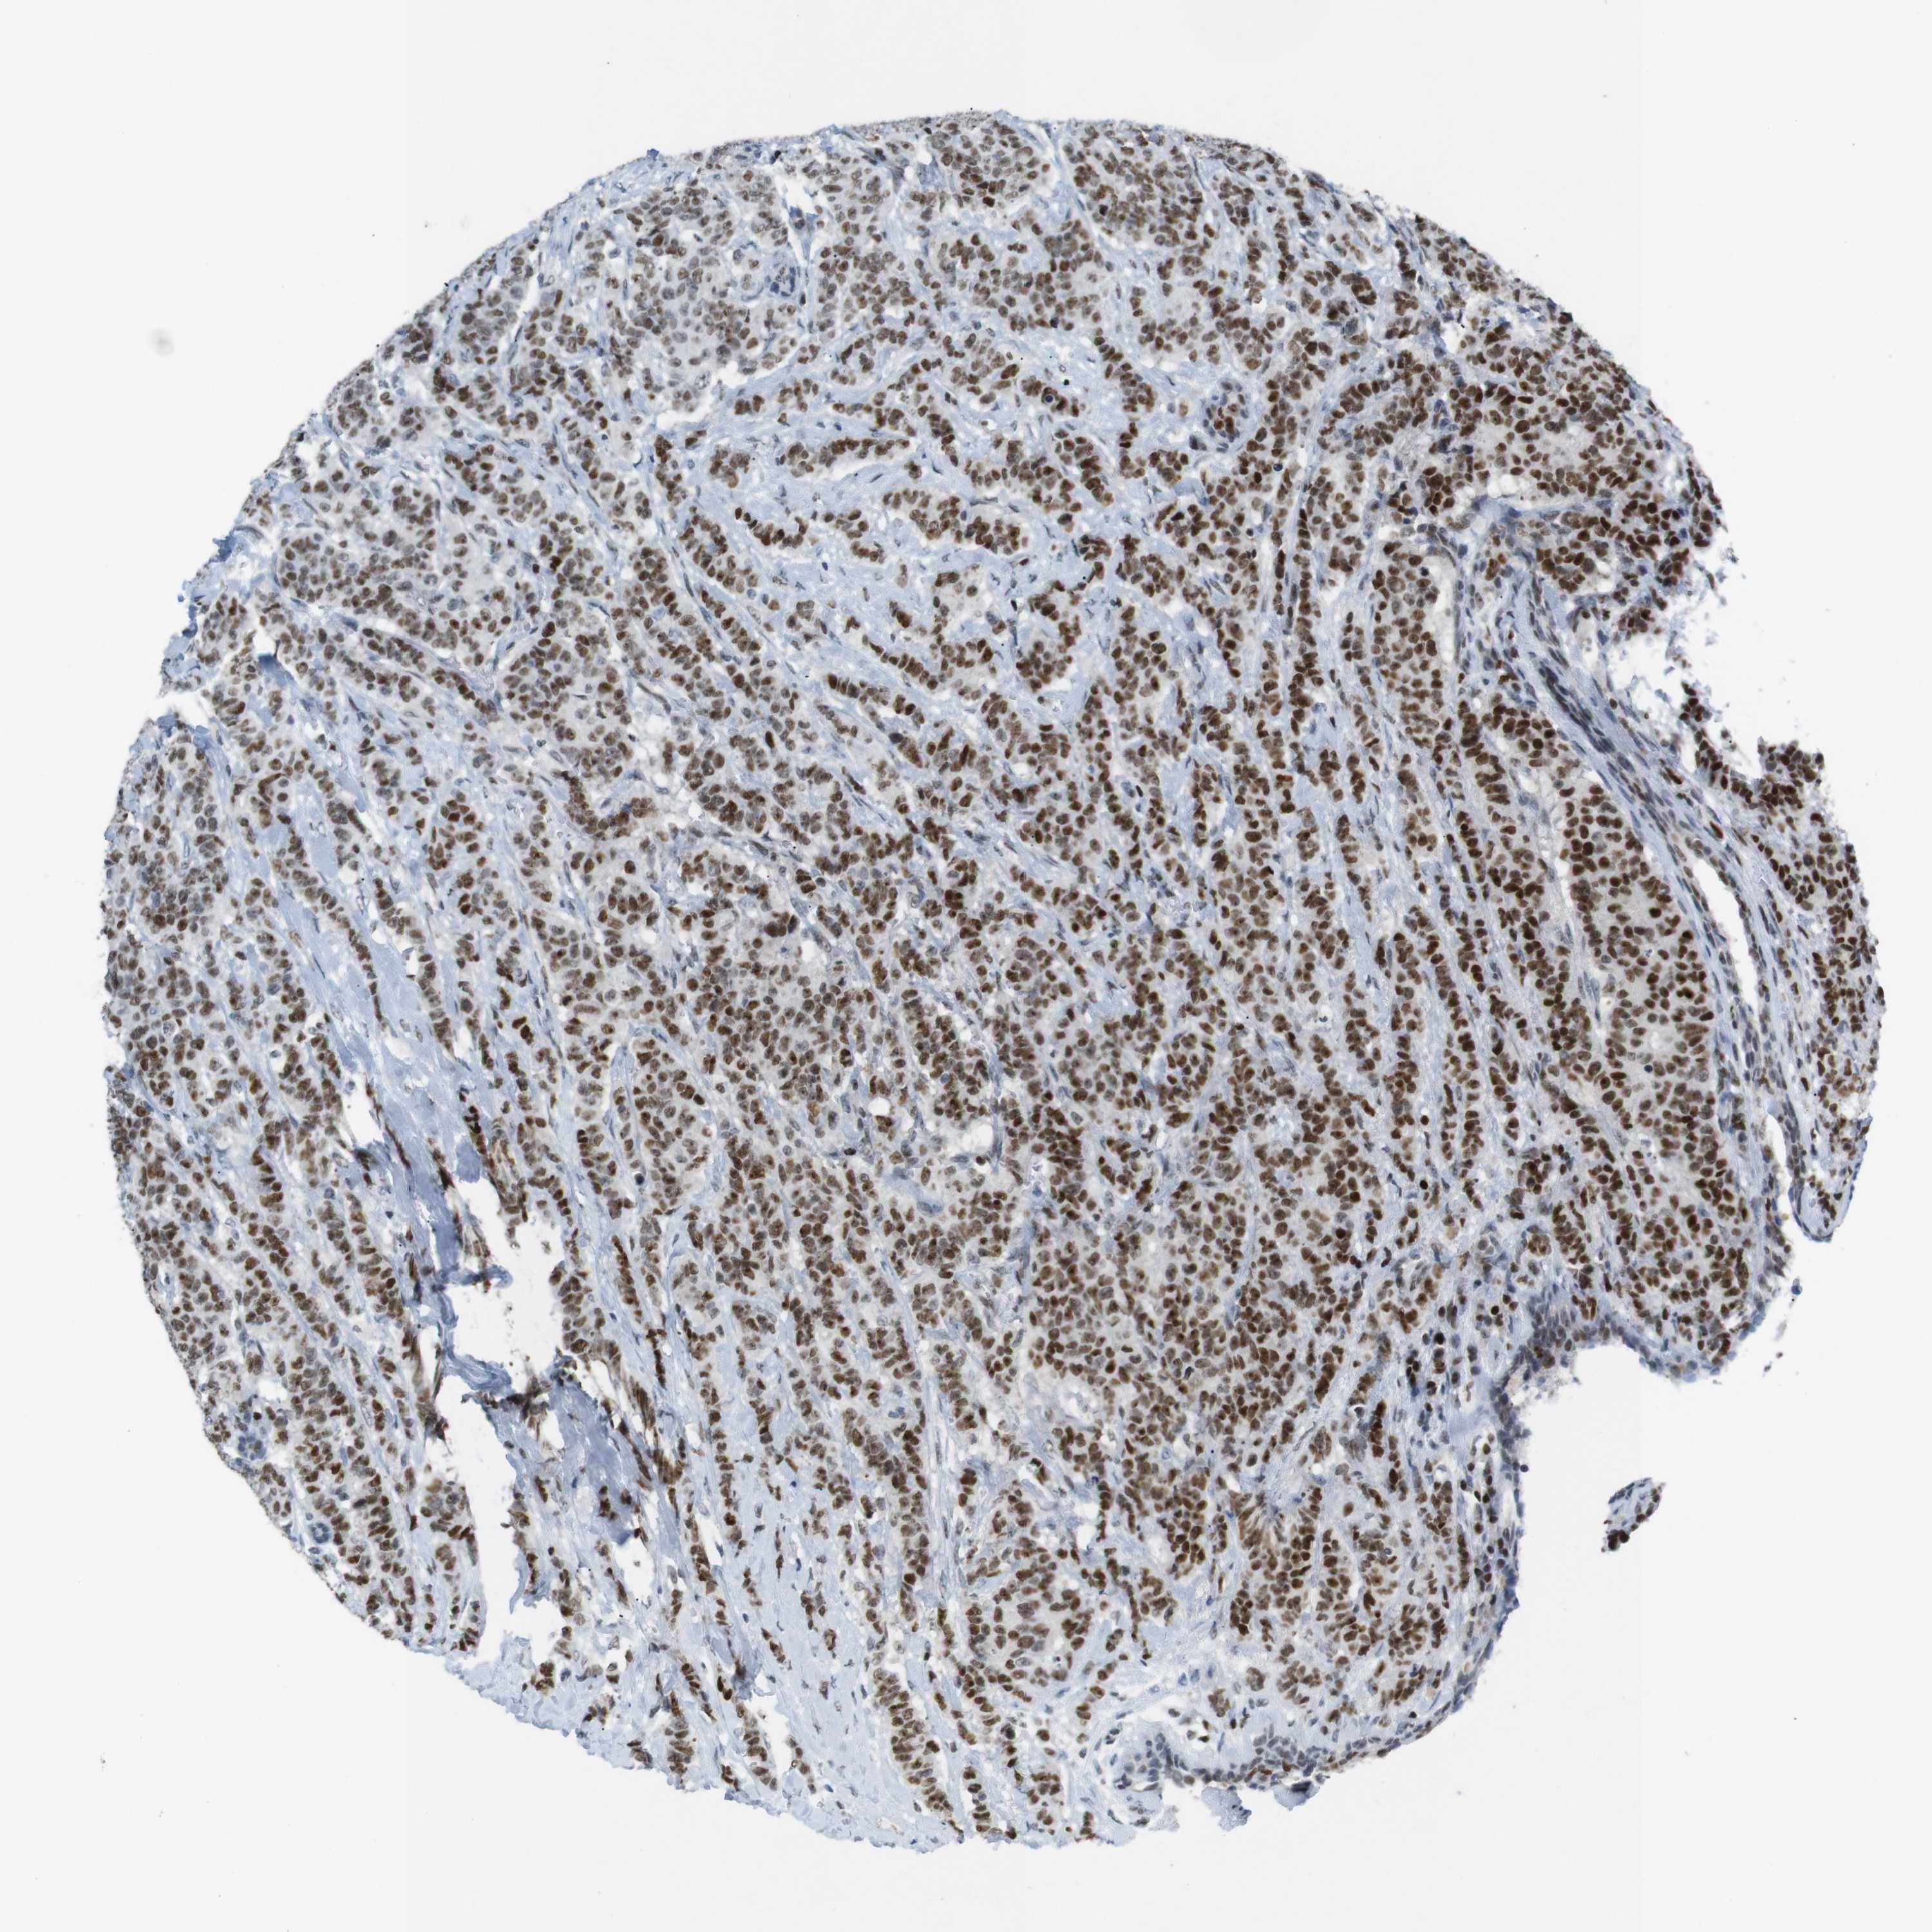

CANCER BREAST CANCER Show tissue menu

BRCA TCGA BRCA VALIDATION PROTEIN EXPRESSION

ANTIBODIES

AND

VALIDATION

RIOX2 is potential prognostic, high expression is unfavorable in Breast Invasive Carcinoma (TCGA)